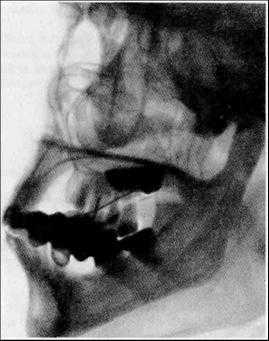

Боковая проекция. На обзорной рентгенограмме черепа в боковой проекции (см. рис. 80) суммарно изображаются обе половины нижней челюсти (77) и височно-нижнечелюстные суставы (78). Поэтому данная проекция может быть использована лишь для выявления грубых травматических повреждений, а также для изучения вырезки нижней челюсти (77ж). Для детального рентгенологического анализа нижней челюсти и суставов производятся прицельные рентгенограммы.

На прицельной рентгенограмме нижней челюсти в боковой проекции(рис. 83а) определяются те же рентгеноанатомические детали, что и на обзорной рентгенограмме черепа в боковой проекции. О правильности укладки судят по четкому изображению прилежащей половины нижней челюсти и отсутствию наслоения на нее противоположной половины.

В связи с уменьшением проекционных наслоений прослеживаются прилежащая к кассете половина тела нижней челюсти (77) и ее ветвь (77в) с венечным (77д) и мыщелковым (77г) отростками, а также

расположенная между ними вырезка (77ж). Передний отдел тела, находящийся ортоградно по отношению к пучку лучей, образует просветление овальной формы с четкими, интенсивными контурами (77и).

Основание нижней челюсти (77а) имеет мощный корковый слой.

Рис. 83. А — прицельная рентгенограмма нижней челюсти в боковой проекции.

77 — тело; 77а — основание; 77в — ветвь; 77г — мыщелковый отросток; 77д — венечный отросток; 77е — угол;

77ж — вырезка; 77и — осевая проекция переднего отдела тела нижней челюсти. Канал нижней челюсти обозначен двойными стрелками.

Альвеолярная дуга нижней челюсти (776) с расположенными в ней зубами свободна от проекционных наслоений только на уровне больших коренных зубов, а на остальном протяжении она перекрыта отдаленной стороной тела нижней челюсти. Структура губчатого вещества нижней челюсти крупнопетлистая; в теле и нижней части ветви определяется канал нижней челюсти (обозначен двойными стрелками) в виде линейного просветления с четкими контурами. В месте перехода тела в ветве по нижнему контуру расположен угол нижней челюсти (77е).

Венечный отросток нижней челюсти четко контурируется (77д), хотя его верхушка проекционно совпадает с углом или ветвью противоположной стороны, реже с бугром верхнечелюстной кости. Мыщелковый отросток нижней челюсти в этой проекции не подлежит рентгеноанатомическому анализу, так как совпадает с изображением верхних шейных позвонков